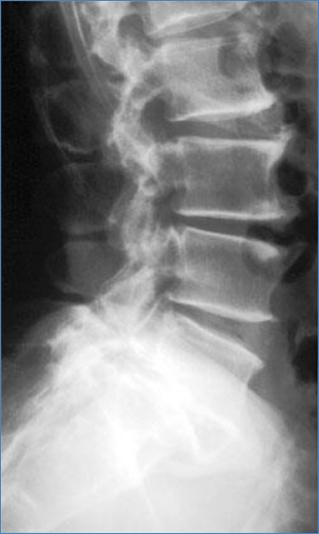

Деформирующий спондилоз

• Выраженные краевые костные разрастания во всех поясничных позвонках.

• Высота дисков сохранена.